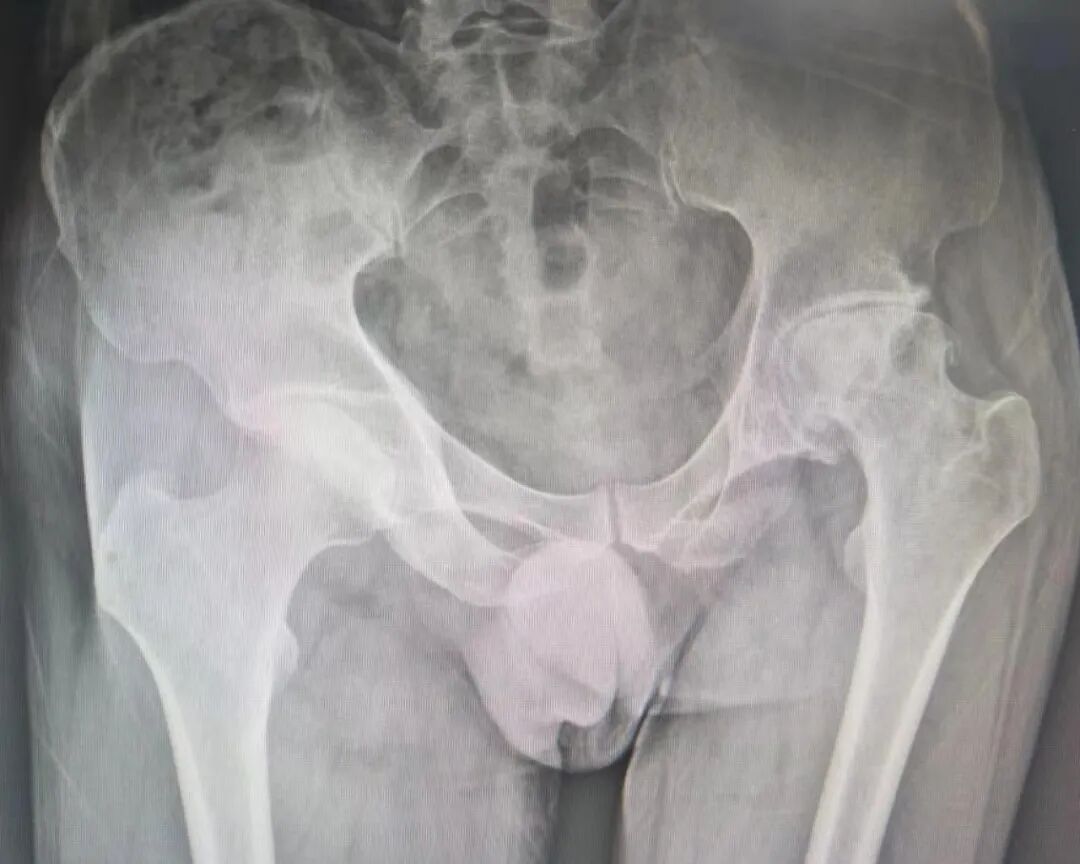

51岁杨某,以”左髋部疼痛伴活动受限多年”主诉入院。入院诊断:左侧股骨头坏死Ⅳ期;神经性皮。骨科鞠健主任团队为患者行左侧全髋关节置换术,其中骨科高值耗材费用从集采前的2.3万元左右,降到了集采后的8500元左右,大大减轻了患者经济负担。

患者术前